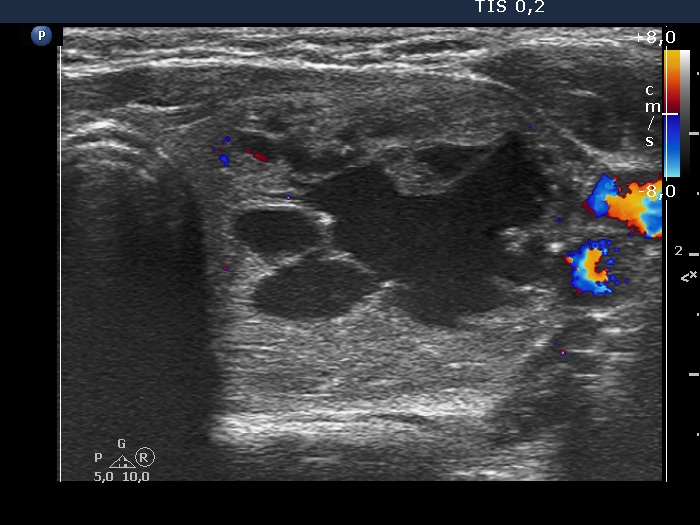

Ultrasonography. The thyroid was echonormal. There was a nodule presenting coarse calcification along its ventral surface. There was a spongiform-type cyst in the left lobe. The nodule has numerous echogenic figures most of them were caused clearly by posterior back wall enhancement.

Eight mL bloody cystic fluid was aspirated. After I aspirated 4 mL fluid, I have noticed that the cyst began to refill at once and a few minutes later the cyst became as large as before the aspiration.